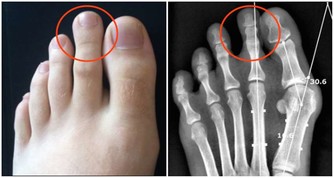

甲狀旁腺分泌的激素的功能為調節鈣的代謝,維持血鈣平衡,分泌不足時可引起血鈣下降,出現手足搐症;功能亢進時則引起骨質過度吸收,容易發生骨折。有時甲狀旁腺1個或全部埋在甲狀腺組織內,使甲狀腺切除手術發生困難。如將些腺全部切除,患者出現鈣代謝失常,發生手足搐搦,嚴重者造成死亡。

甲狀旁腺被拿掉了,必然影響全身鈣質的吸收,就要終生補鈣。長期缺鈣對身體的影響是巨大的,甲狀旁腺的功能是強大的,損失了它,代價是巨大的。短時間的血鈣低身體就會發麻,抽搐,長期的缺鈣會導致骨密度降低,引起骨質疏鬆,你就是那個一碰就碎的玻璃人。輕輕的一個跟頭,就能斷了胳膊腿。

第一次手術我的左側甲狀旁腺就被拿掉了,但是我不知道,醫生也沒有醫囑。在那個年代也沒有補鈣的概念的。我記得大肆廣告補鈣是在95、96年,我87年做的手術時可沒人給我說過這個事情。幸好我右側的甲狀旁腺保留了,它的功能也有了代償。所以沒有發生過抽搐等現象。但是其實身體是出於缺鈣的症狀的,我的腳趾甲就沒長起來,只有兩個大腳趾有指甲。

萬幸我的個子是長起來了,165cm,算是中等個了。由於無知,上大學時偷偷停了半年的藥,我就是不想終生服藥,想看看停藥有什麼不行的。半年後,甲減的症狀越來越明顯了,出現了思維跟不上的情況,明顯反應遲鈍。更壞的結果很快就來了,在一次體育跳遠課上輕輕的一跳,就跳成了左腿脛骨粉碎性骨折,打了一個月石膏。後來經過一年的康復鍛煉,腿才又恢復了。我從骨折後有開始恢復服甲狀腺素片了。甲狀腺癌復發有可能是從那時開始的。

在去年的第二次手術,做右側甲狀腺摘除時就把甲狀旁腺也摘除了。這下我的身體就一點甲狀旁腺都沒有了。它的反應非常明顯,而且迅速。手術當晚就因血鈣的迅速流失,腰椎疼了一晚上,直到第二天早上醫生查房後,給我靜脈注射了葡萄糖酸鈣,才止住了疼。